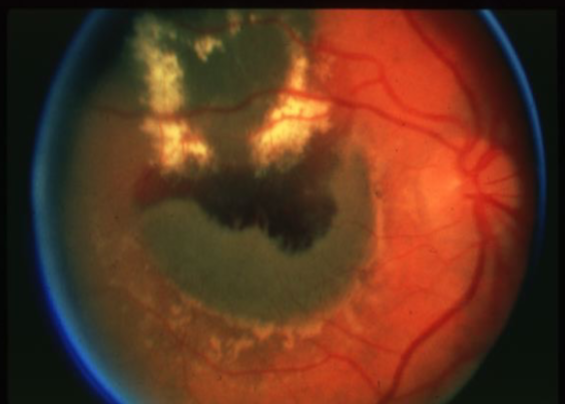

metastatic carcinoma

metastatic carcinoma

metastatic carcinoma

metastatic carcinoma

metastatic carcinoma

metastatic carcinoma

metastatic carcinoma

metastatic carcinoma

metastatic carcinoma

metastatic carcinoma of choroid

more common than primary malignancies

seed of cancer that started in a cancer elsewhere & spread to eye via blood flow

features:

cream, yellow, light brown

flat or slightly elevated mottled pigment clumping on surface

extensive exudative RD

maybe multifocal or bilateral